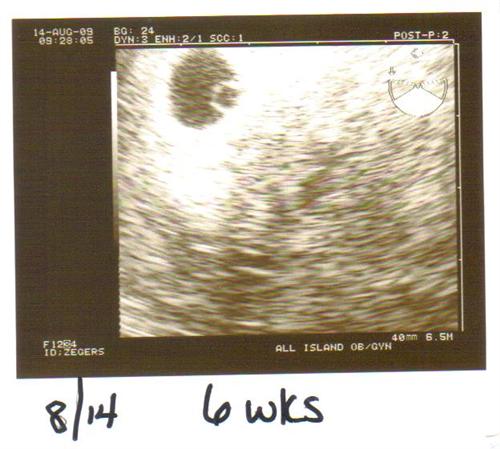

6 weeks